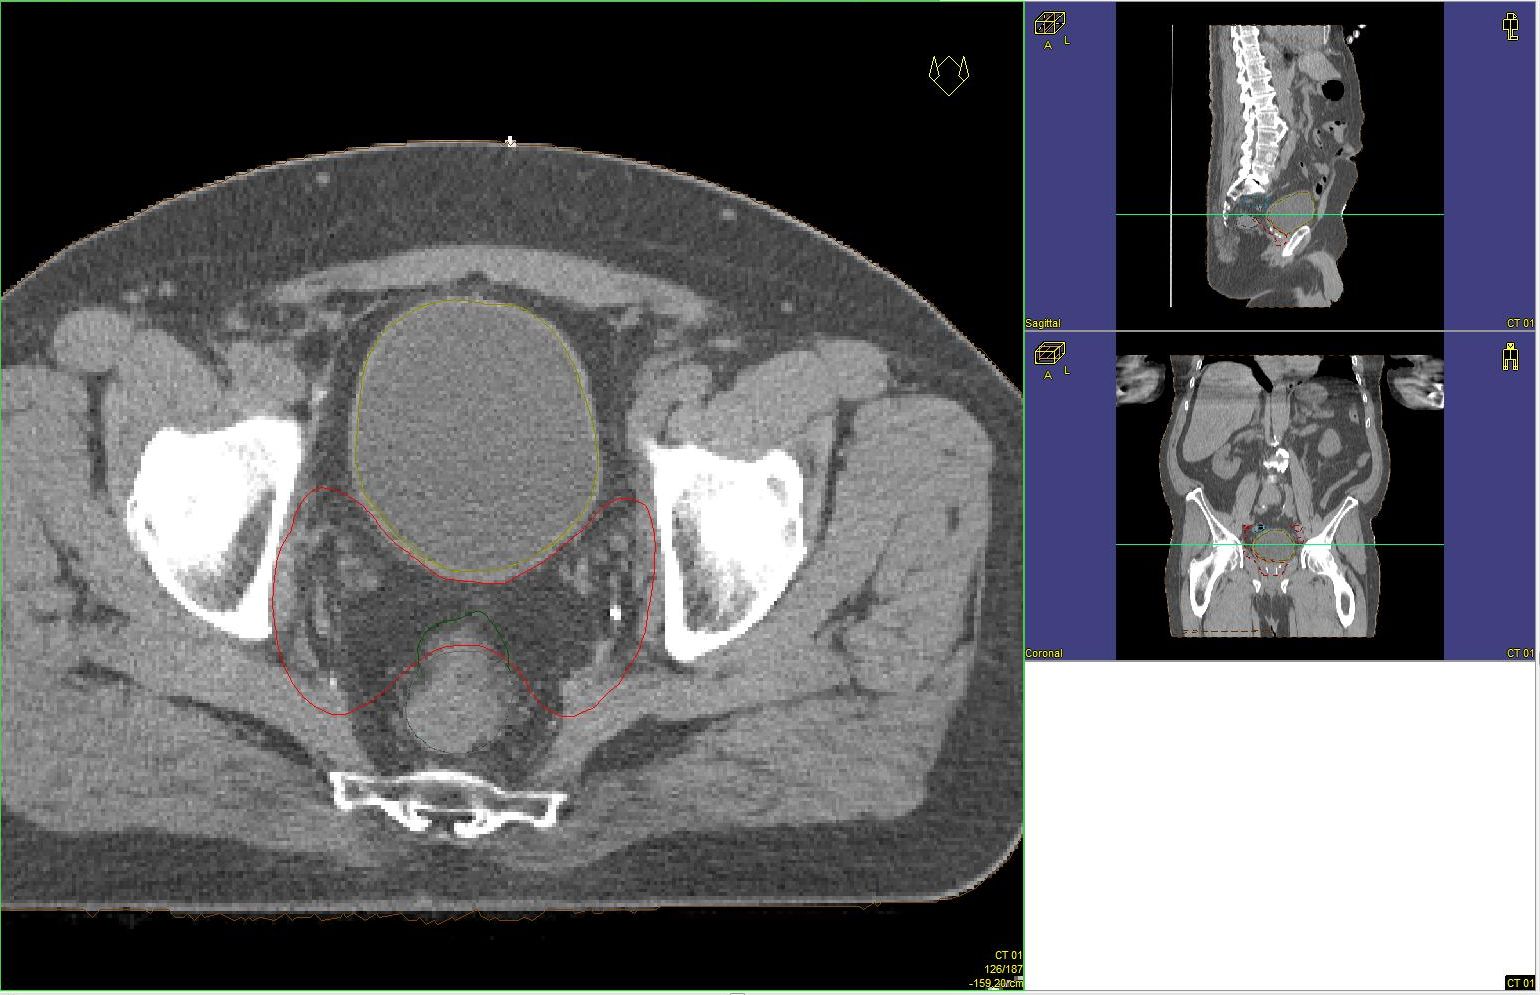

Prostata-Ca: Zielvolumen der postoperativen Radiotherapie

Beispiel: postoperative RT